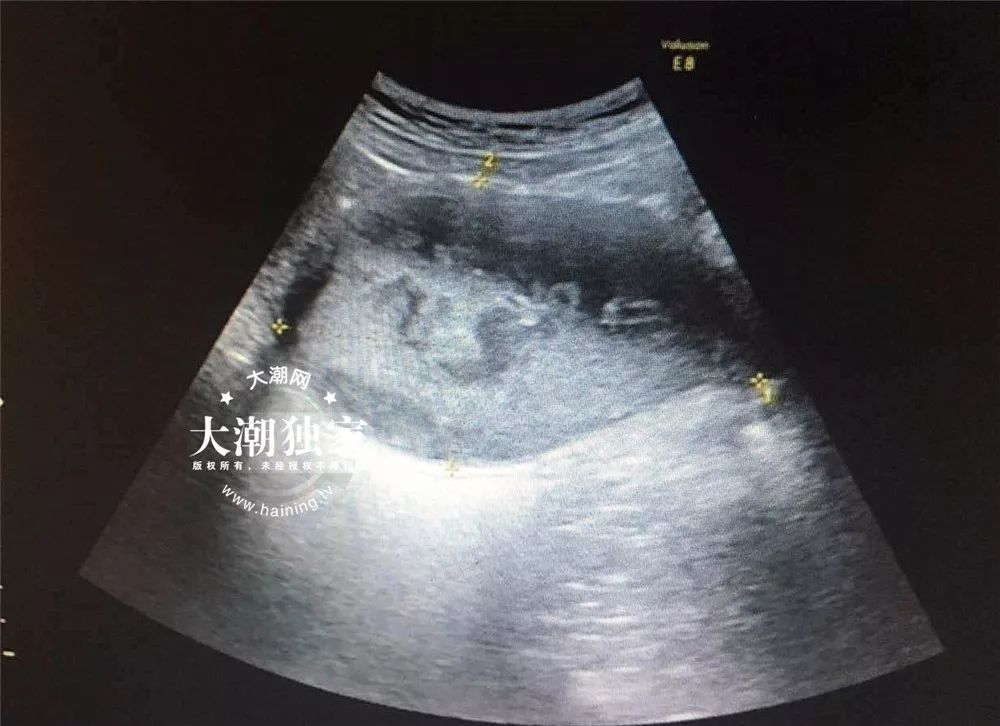

小燕到底怎么了?接诊的医生询问了小燕的病情后,当场就觉得小燕的情况有些特别,于是马上给小燕安排了B超和妇科检查。

B超报告

根据检查,医院妇科主任俞丽娟判断,小燕得了处女膜闭锁伴盆腔感染!需要马上住院进行手术治疗。